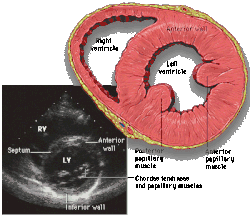

![]() Subcostal four chamber | ![]() Apical four chamber | ![]() Parasternal long axis | ![]() Parasternal short axis | ||||||||

Each figure contains a TTE with a black background, and a corresponding colored illustration. | Patrick J. Lynch and C. Carl Jaffe, Yale University, 2006. | ||||||||||

Click on a figure to enlarge it and see some parts of the heart identified. RV, right ventricle; LV, left ventricle; RA, right atrium; LA, left atrium; TV, tricuspid valve; MV, mitral valve; AV, aortic valve; RVOT, right ventricular outflow tract; LVOT, left ventricular outflow tract |